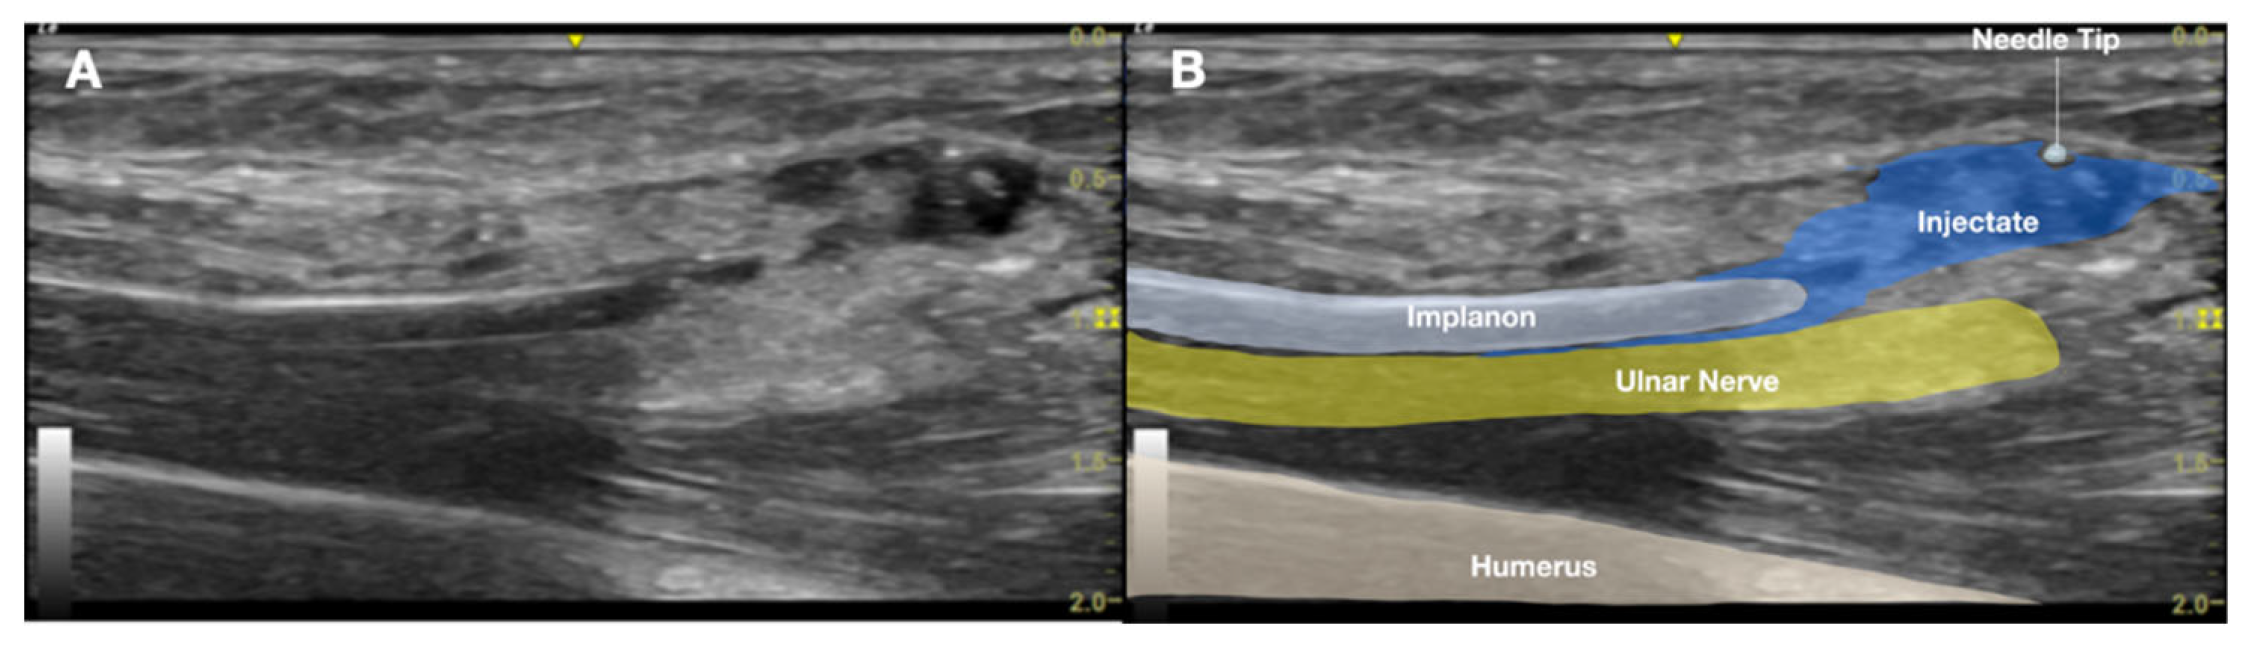

The US findings localized the echogenic structure beneath the muscle layer, adjacent to the ulnar nerve, within the neurovascular bundle of the upper arm (Figure 4, Figure 5A). No neuroma or nerve enlargement was observed; however, dynamic US demonstrated apparent direct contact between the implant and the nerve sheath. The clinical impression was of a migrated, deeply seated, and unstable implant in close proximity to the ulnar nerve. Intermittent nerve irritation or impingement, likely exacerbated by daily movement and previous failed removal attempts, was considered the probable cause of her neuropathic pain. After obtaining informed consent, the decision was made to pursue minimally invasive, US-guided removal as an alternative to open surgical exploration.

Figure 4. Long-axis ultrasound image of the medial arm demonstrating the Implanon® device positioned deep into the muscle layer adjacent to the ulnar nerve within the neurovascular bundle. A).Ultrasound image; B). Labeled explanation.

Figure 5. A: Close relationship between Implanon® and the ulnar nerve. B: Stabilization of one end of the Implanon device with a 25G needle. C: Removal of Implanon.